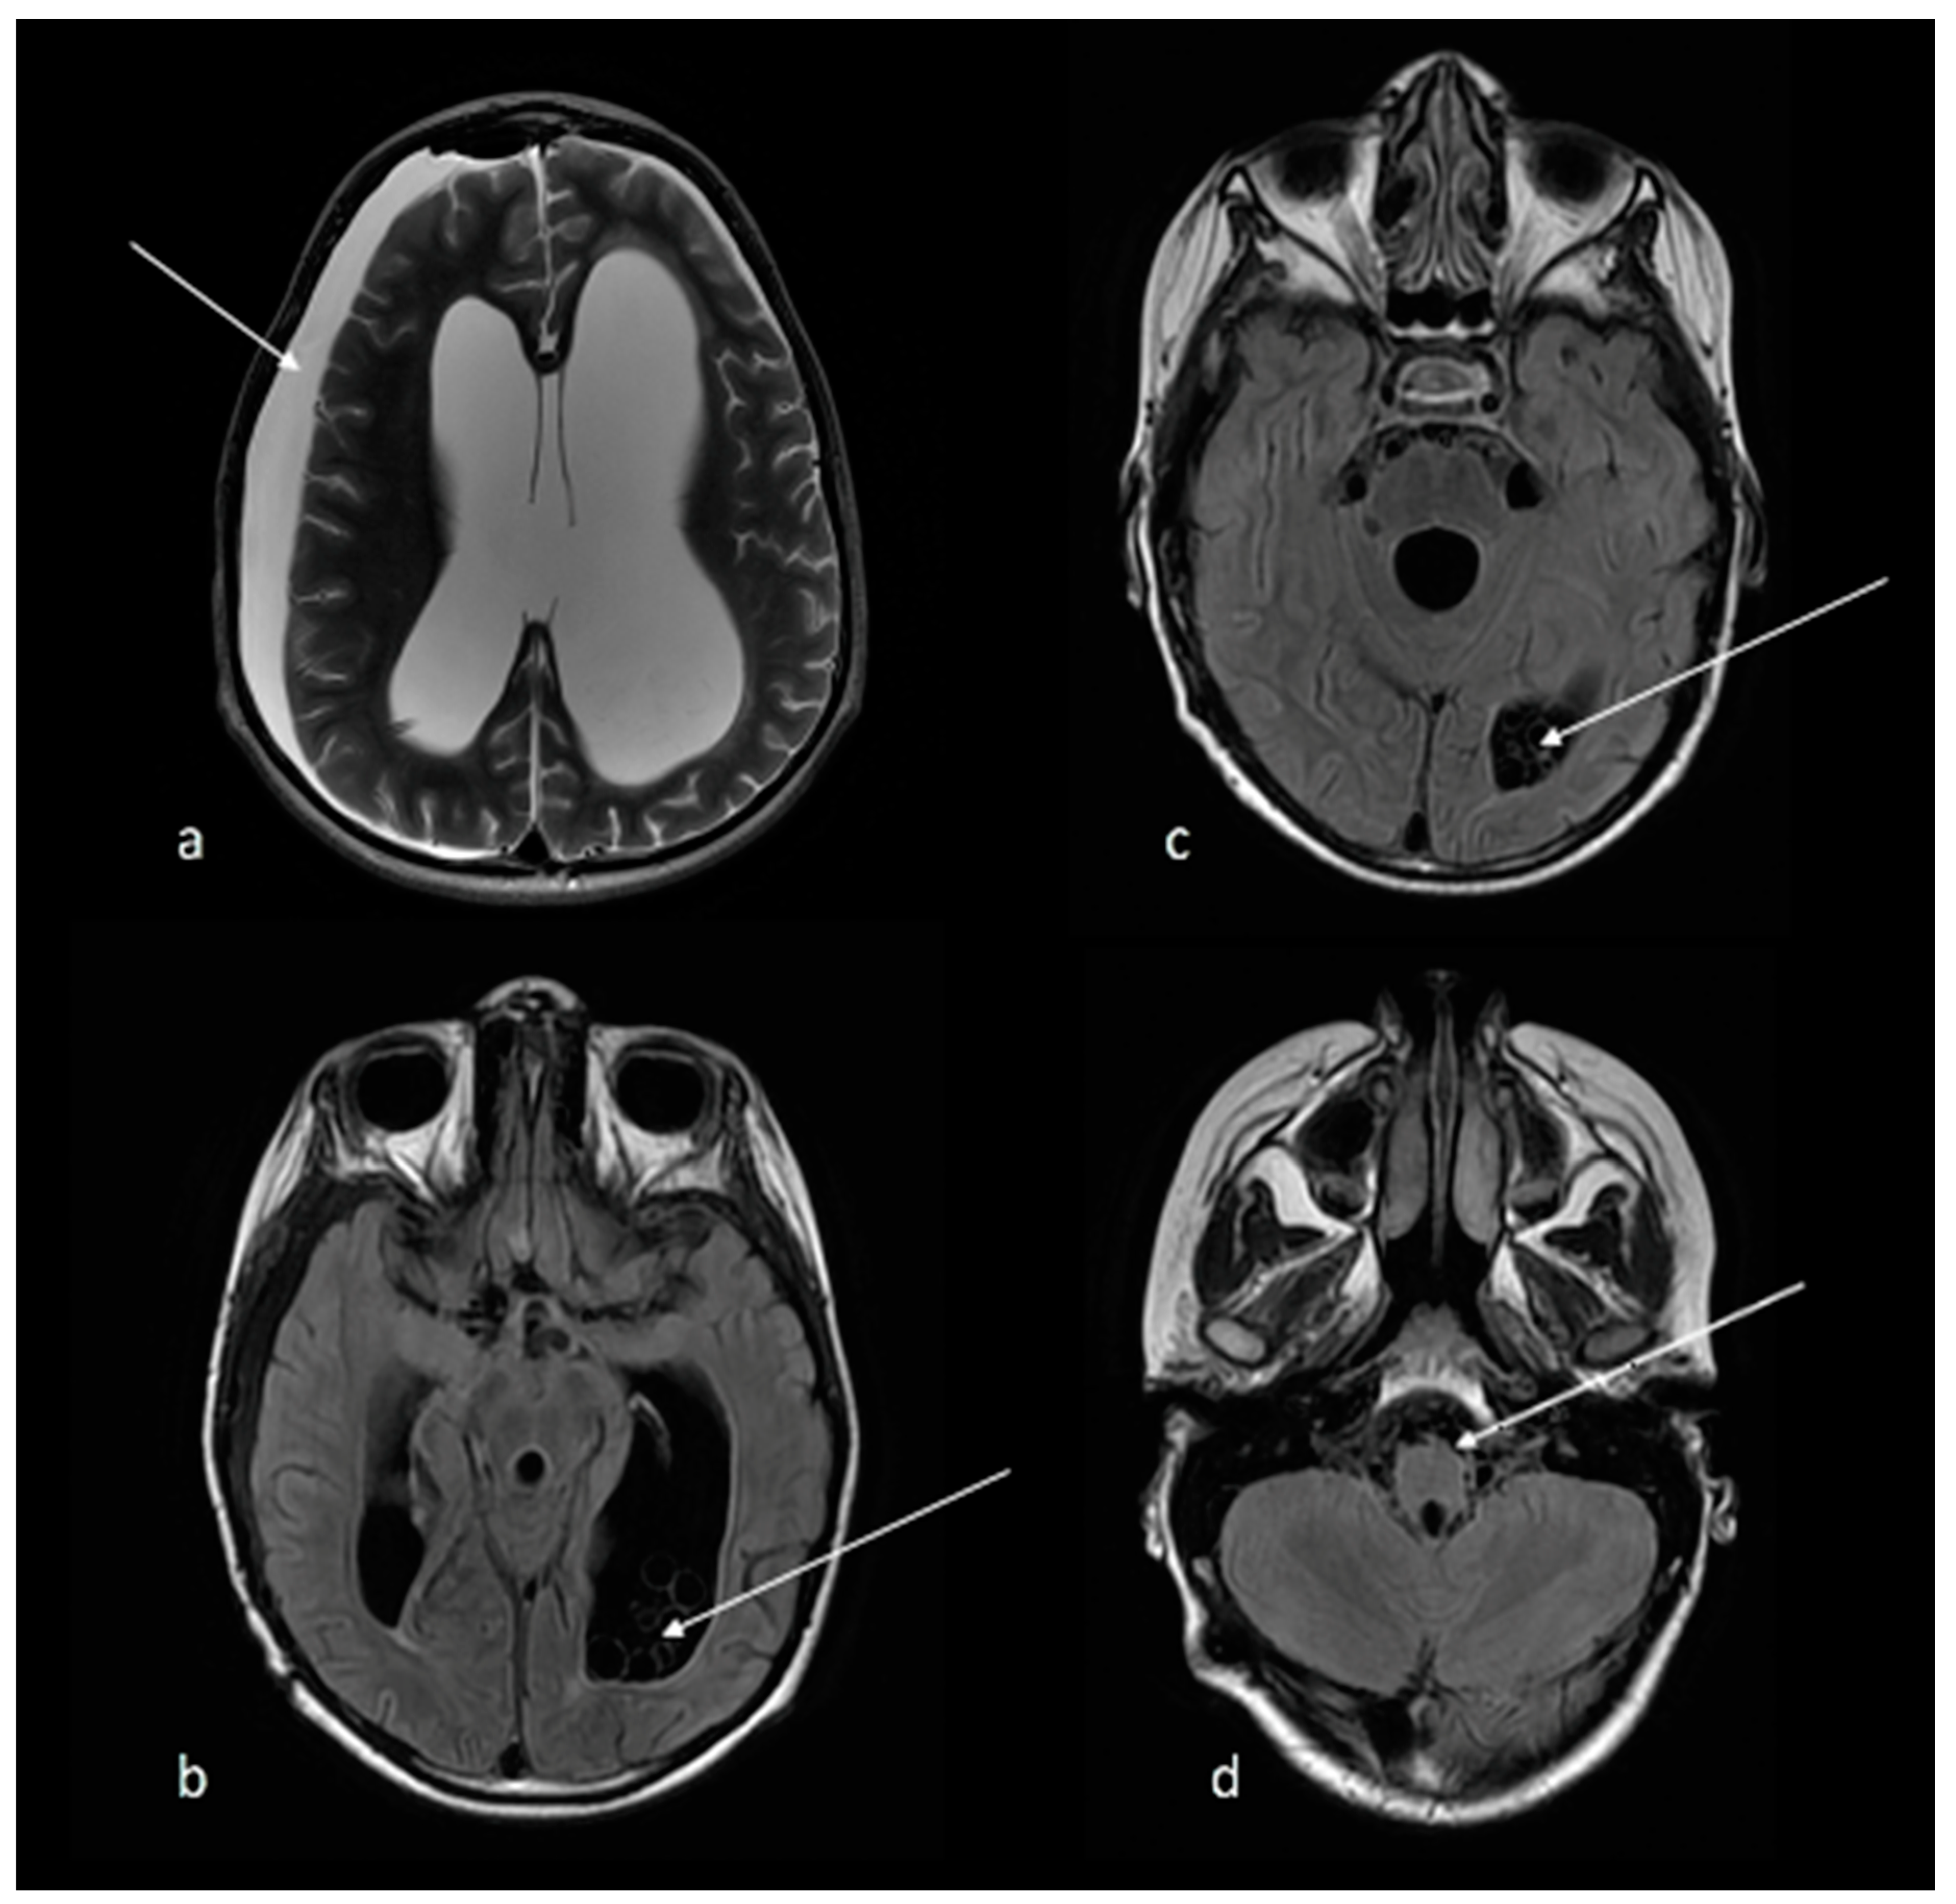

2. Case Report